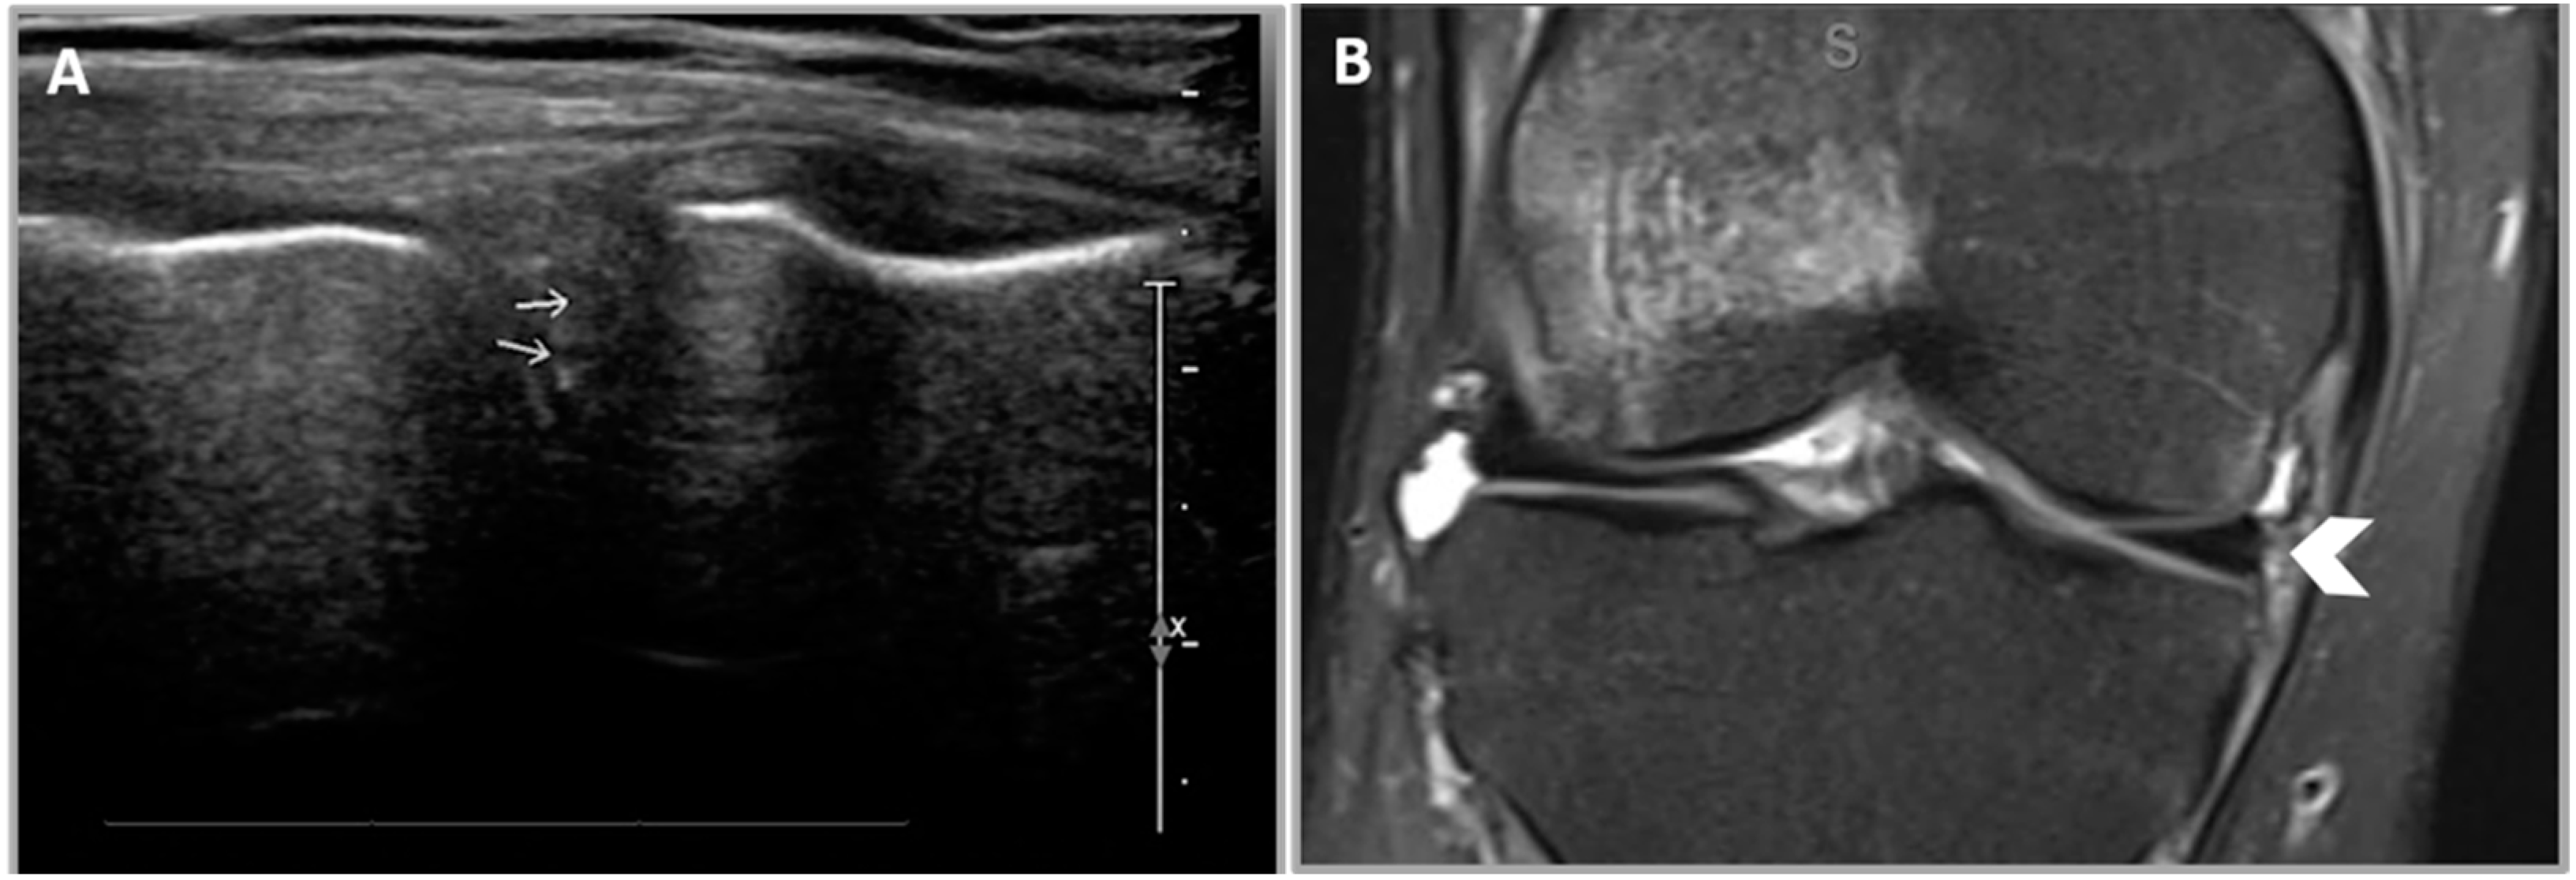

2.5.3. Criterion 3—Diminutive Meniscus

2.5.4. Criterion 4—Displaced Meniscal Fragment

2.5.5. Criterion 5—Extruded Meniscus